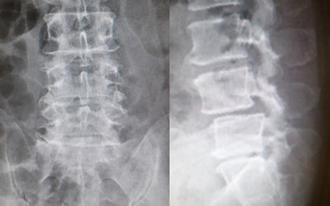

第4腰椎に前屈時に増強するすべりを認め不安定性を示しています。 -